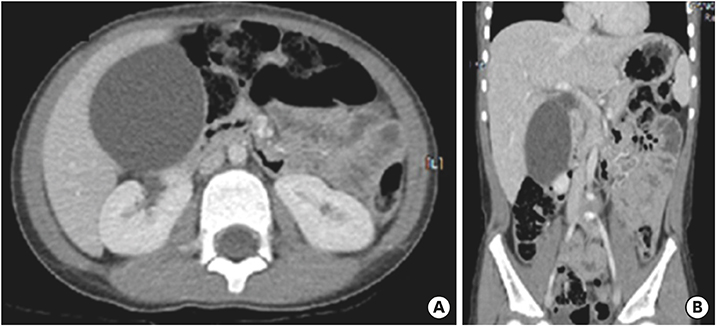

On the first day after admission, he received 2 g/kg IVIG and 50 mg/kg/day aspirin, following which his fever subsided and no further IVIG treatment was needed. His first echocardiography showed myocarditis (ejection fraction [EF], 45%) and mild ectasia of left main coronary artery (3.2–3.4 mm in diameter). On the second day after his admission, echocardiography (second follow-up) showed improved mild myocarditis (EF, 55%), improved ectasia of left main coronary artery (2.7–2.8 mm in diameter), and severe GB distension (8.9×4.6 cm in size), which possibly indicated GB hydrops (Fig. 2A). On the fourth day after his admission, although he had no fever and exhibited improvements in KD symptoms (i.e., eye injection, rash on abdomen, and cervical lymphadenopathy), he still complained of abdominal pain, distension, and tenderness of the RUQ. Follow-up laboratory findings were improved: neutrophilic leukocytosis (6,130 cells/mm3, with 33% neutrophils); decreased CRP (4.4 mg/dL), BNP (347 pg/mL), AST (40 U/L), and ALT (72 U/L); and improved hyperbilirubinemia (total bilirubin, 0.7 mg/dL). Echocardiography (third follow-up) showed normal completely improved carditis and still severe GB distension (10.2×5.5 cm in size) (Fig. 2B). Abdominal ultrasonography (US) was performed, which showed a markedly distended GB without stone, sludge, or wall thickening as well as normal bile ducts and liver morphology, which confirmed GB hydrops (Fig. 3A). On the sixth day after his admission, although his signs of KD had nearly disappeared, he still complained of abdominal discomfort, which had been moderately improving. The second follow-up abdominal US revealed a no notable change in GB distension compared to previous sonographic findings (Fig. 3B). An abdominal computed tomography (CT) scan was also obtained to exclude other hepatobiliary abnormalities, which showed similar findings as sonography, including a marked dilatation of the GB (8.0×5.5 cm in size) without stone, sludge, or wall thickening as well as normal bile ducts and liver morphology (Fig. 4). No complications necessitating surgical intervention had occurred and he was discharged 7 days after admission with only mild tenderness on the right upper-mid quadrant.

Fig. 3

Abdominal ultrasonography showed severe gallbladder distension (A) 9.8×4.9 cm in size and (B) 9.3×4.3 cm in size.